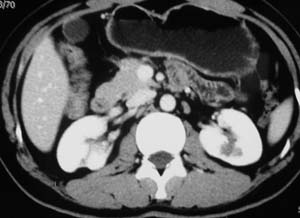

以下是引用子期在2010-3-19 20:47:00的发言:[br]血管畸形的ct增强应该有明显强化,本例并不相符合。本例双肾局部的略低密度影,累及肾盂,局部皮质明显变薄、内陷,增强扫描有轻度的强化,应考虑为炎性病变,患者为年轻男性,累及双肾的感染以结核较常见,可以没有明显的临床症状,尿中有时候也并不能查出什么;肾脓肿常有明显感染中毒症状,本例不符,另外一般的肾盂肾炎或肾小球肾炎通过小便就可确诊,其它还不能排除的是黄色肉芽肿性肾盂肾炎,然而单凭ct一般也很难鉴别。